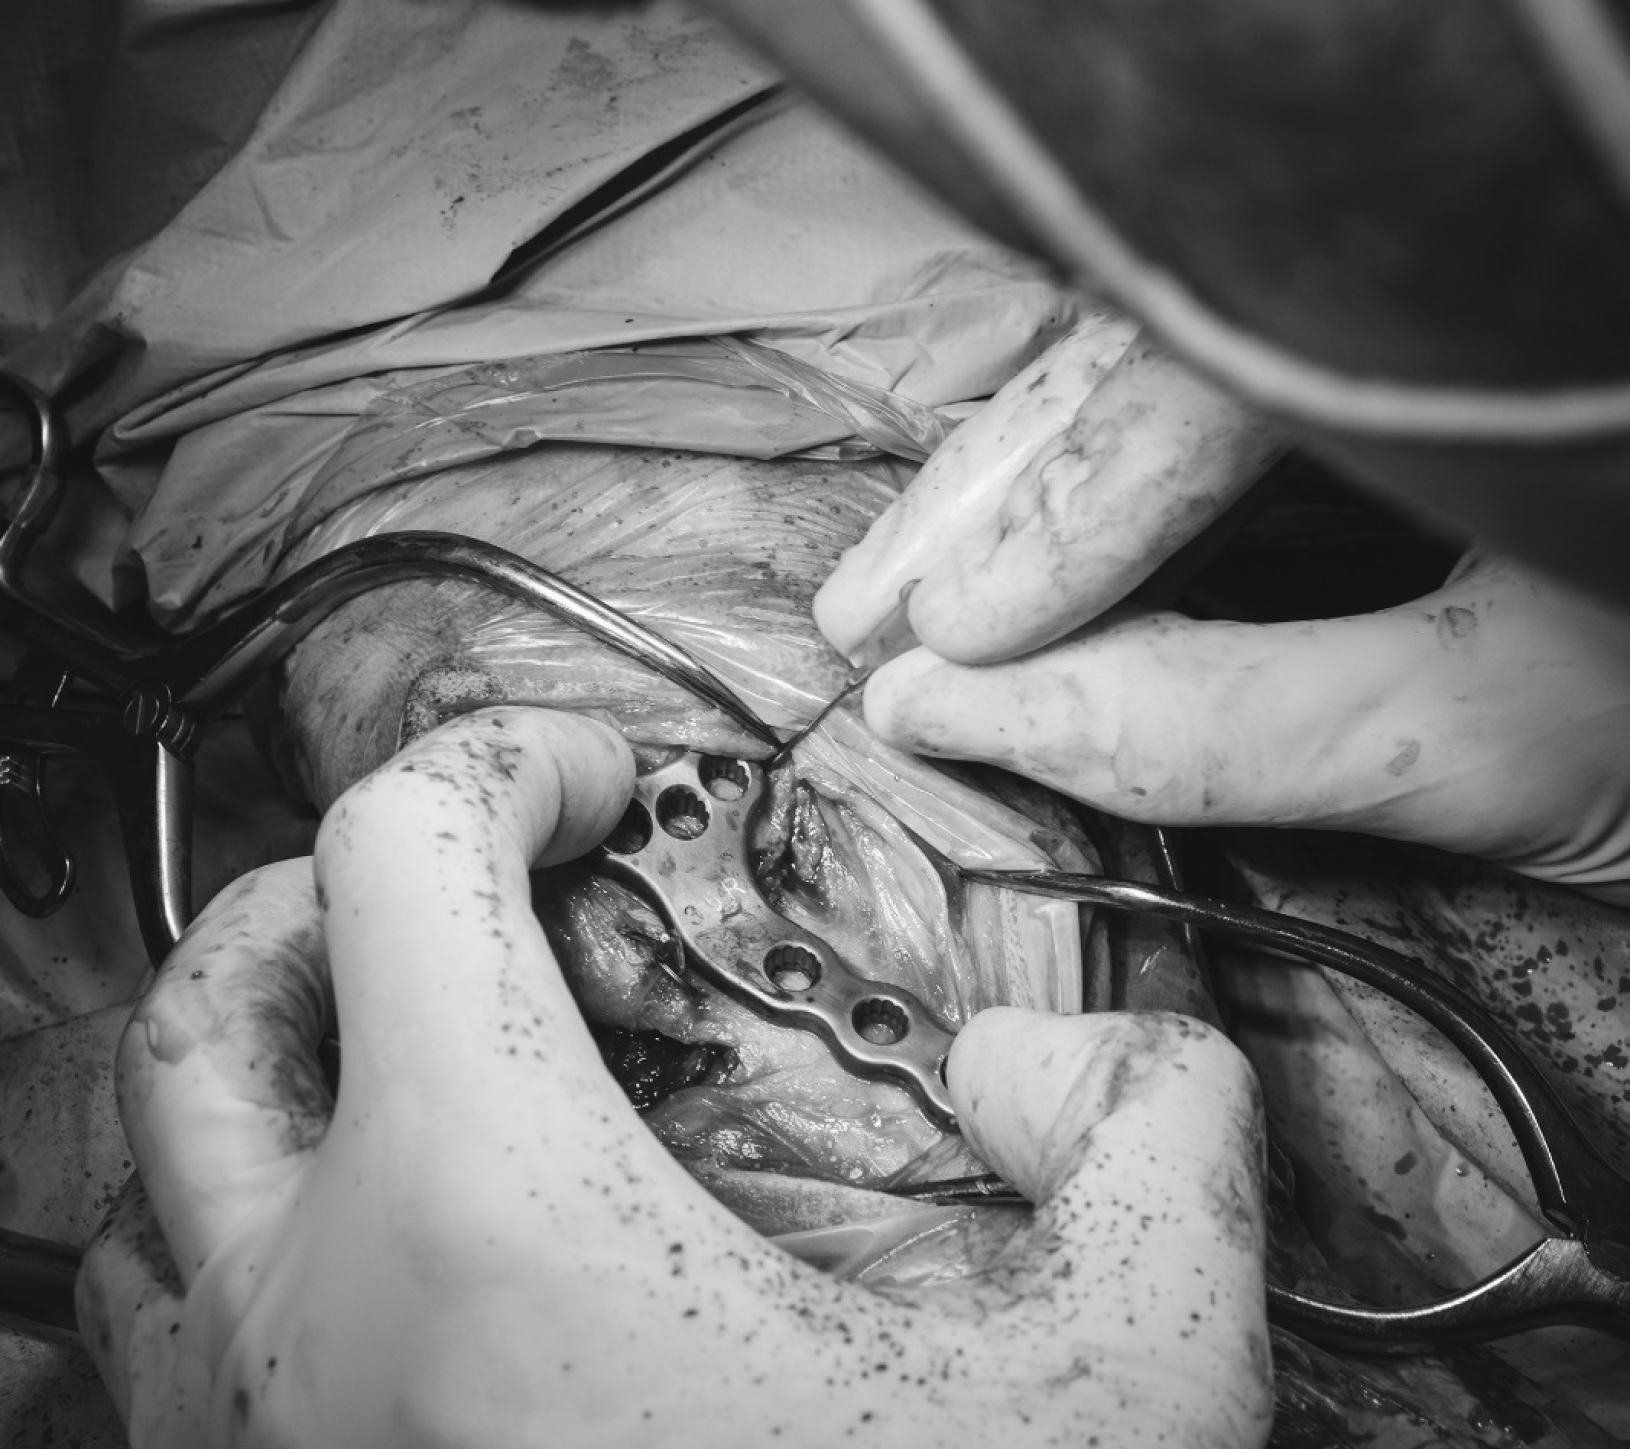

- Fijación interna: consiste en la utilización de implantes (como placas y tornillos, agujas o clavos intramedulares entre otros) que se colocan directamente sobre o dentro del hueso para estabilizar los fragmentos óseos de una fractura.

- Minimally Invasive Plate Osteosynthesis (MIPO): minimiza la invasion quirúrgica al reducir la necesidad de grandes incisiones y abordajes pero requiere de una evaluación y planificación prequirúrgica exhaustiva. Generalmente se realizan pequeñas incisiones en los tejidos próximos a los fragmentos óseos a estabilizar, y se procede a la reducción de la fractura, idealmente asistida por un fluoroscopio que garantice el óptimo alineamiento óseo. Habituamente se premoldea una placa de osteosíntesis que se desliza a través de las pequeñas incisiones creadas sobre los fragmentos de hueso y se fija a los mismos utilizando tornillos. En último lugar se suturan las incisiones creadas. La menor agresión quirúrgica puede favorecer una recuperación mas rápida y predisponer a menos complicaciones postquirúrgicas. Sin embargo, no todas las fracturas se pueden manejar mediante esta técnica.